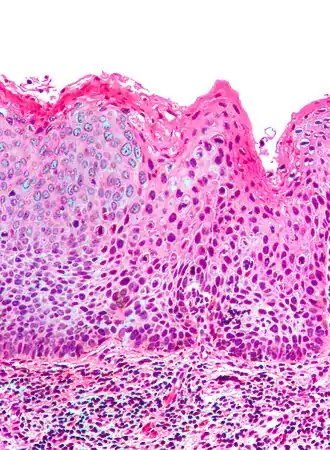

![]() Micrografía de una NIV III. Tinción H&E. | ||

En medicina, el término neoplasia intraepitelial vulvar (NIV) denota una lesión del epitelio escamoso de la vulva que se caracteriza por displasia con varios grados de atipia entre el epitelio originándose desde la lámina basal, la cual permanece intacta, de modo que no es una enfermedad invasiva, como el cáncer, aunque tienen un conocido potencial de volverse maligno.

- NIV III, más severa, incluyendo el carcinoma in situ de la vulva